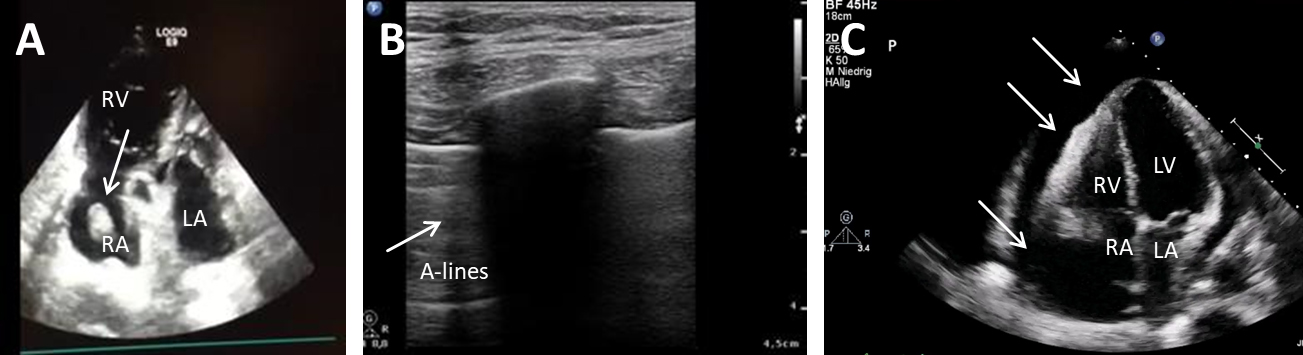

It has been shown decades ago that transthoracic echo (TTE) is sensitive and

specific for cardiac tamponade and can be used to measure the effusion volume

[37, 38]. Flow over the mitral- and trikuspidal-valve are dependent on in- and

expiration and differences are increased in pericardial effusion [39]. Today,

hemodynamic relevant tamponades are characterized by complete collapse of the

right atrium (

Fig. 2.Ultrasound in obstructive shock. (A) TTE shows a wormously configured thrombus in the right atrium with clearly dilated right ventricles and completely emptied left ventricle. RA, right atrium; RV, right ventricle; LA, left atrium. (B) Lung sonography (LUS) shows A-lines and a missing lung sliding (white arrow), while lung on the right side is normal. (C) TTE shows a large pericardial effusion (white arrows) with swinging heart. RA, right atrium; RV, right ventricle; LA, left atrium; LV, left ventricle.